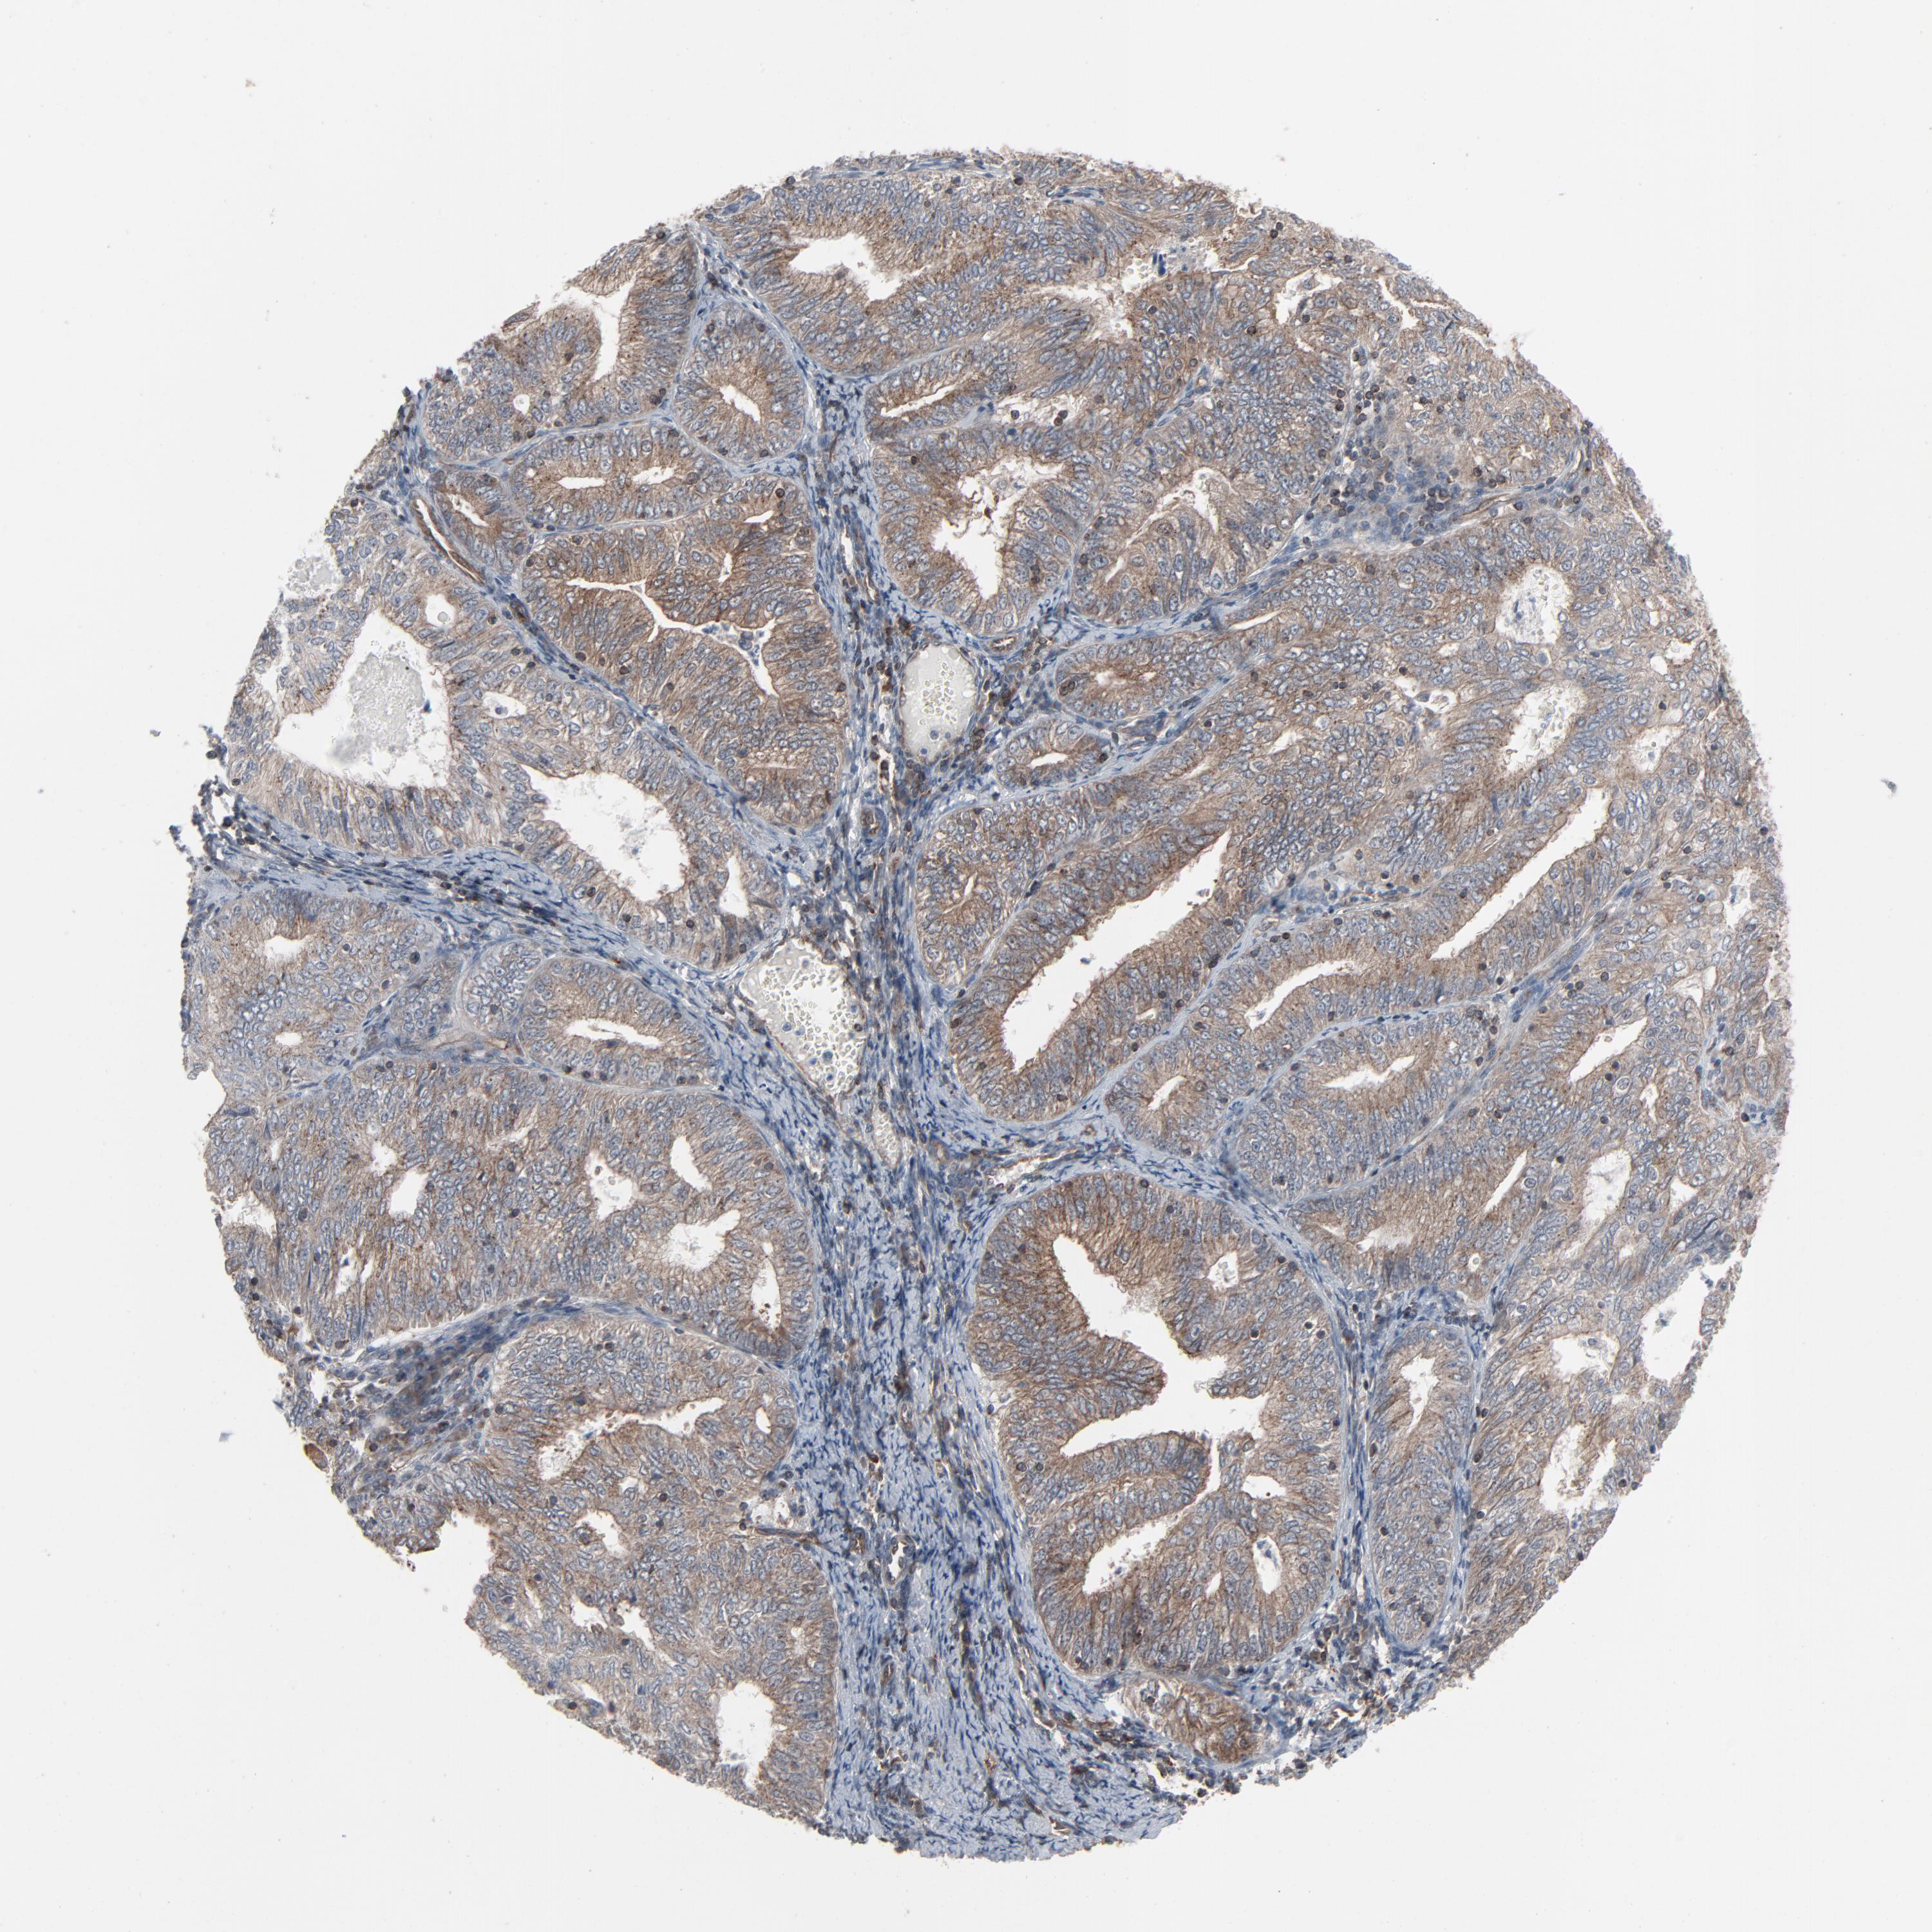

ENDOMETRIAL CANCER - Protein expressioni

A mouse-over function shows sample information and annotation data. Click on an image to view it in a full screen mode. Samples can be filtered based on level of antibody staining by selecting one or several of the following categories: high, medium, low and not detected. The assay and annotation is described here.

Note that samples used for immunohistochemistry by the Human Protein Atlas do not correspond to samples in the TCGA dataset.

Antibody stainingi

Antibody staining in the annotated cell types in the current human tissue is reported as not detected, low, medium, or high, based on conventional immunohistochemistry profiling in selected tissues. This score is based on the combination of the staining intensity and fraction of stained cells.

Each image is clickable and will lead to virtual microscopy that enables deeper exploration of all samples and also displays staining intensity scores, fraction scores and subcellular localization as well as patient and tissue information for each sample.

Antibody HPA003279

Antibody HPA003360

Antibody CAB019303

Staining

High

Medium

Low

Not detected

Intensity

Strong

Moderate

Weak

Negative

Quantity

>75%

75%-25%

<25%

None

Location

Nuclear

Cytoplasmic/membranous

Cytoplasmic/membranous,nuclear